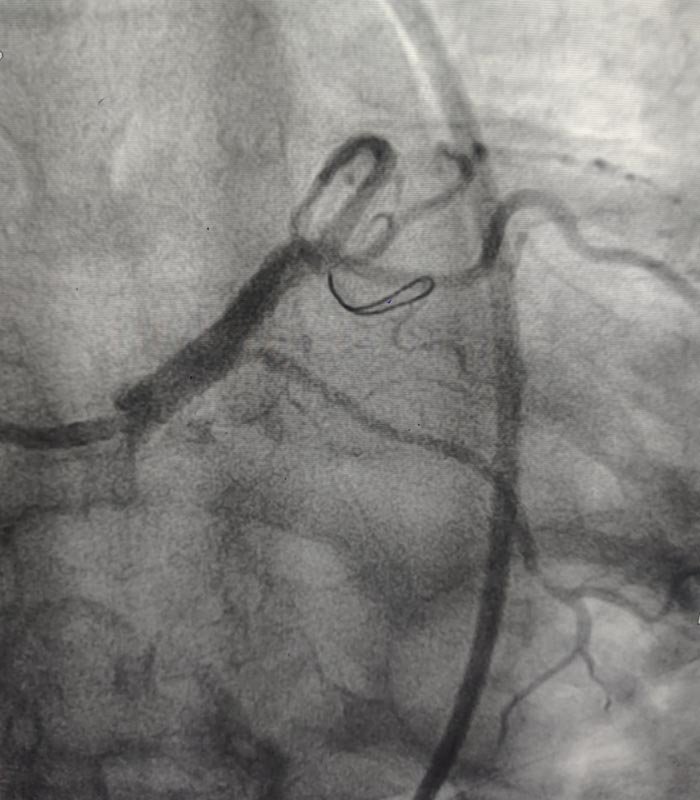

Coronary angiography (CAG) revealed a critical ostial stenosis of the left main coronary artery, a lesion known for its prognostic significance and high mortality risk if left untreated. Left main disease, especially in elderly patients, demands careful evaluation and individualized decision-making.

Technique Performed: Complex High-Risk Left Main PCI

The procedure was planned with extreme caution, focusing on safety, precision, and optimal outcomes. Key aspects of the intervention included:

• Careful lesion assessment of the left main ostium

• High-risk PCI strategy with meticulous guide catheter support

• Precise lesion preparation to ensure optimal stent expansion

• Accurate stent deployment across the critical left main lesion

• Optimization of final results to achieve excellent angiographic flow

Special attention was paid to minimizing contrast load due to the patient’s CKD, while ensuring procedural success. The intervention resulted in excellent restoration of coronary blood flow with no procedural complications